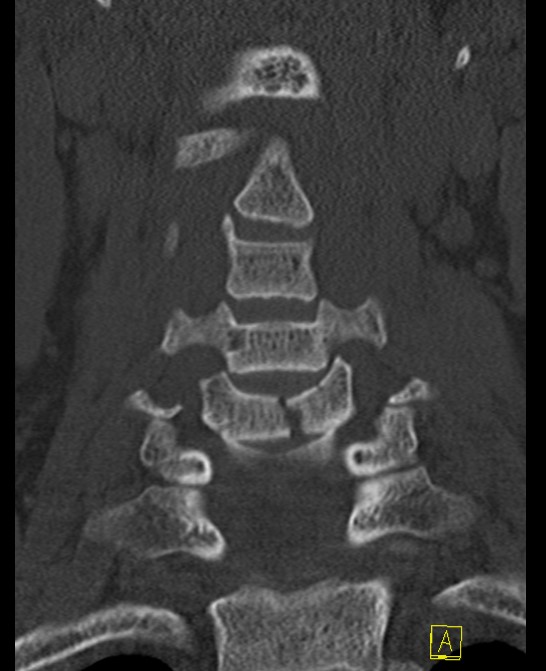

CT

MRI

Assess integrity of posterior column

Evaluate cord injury